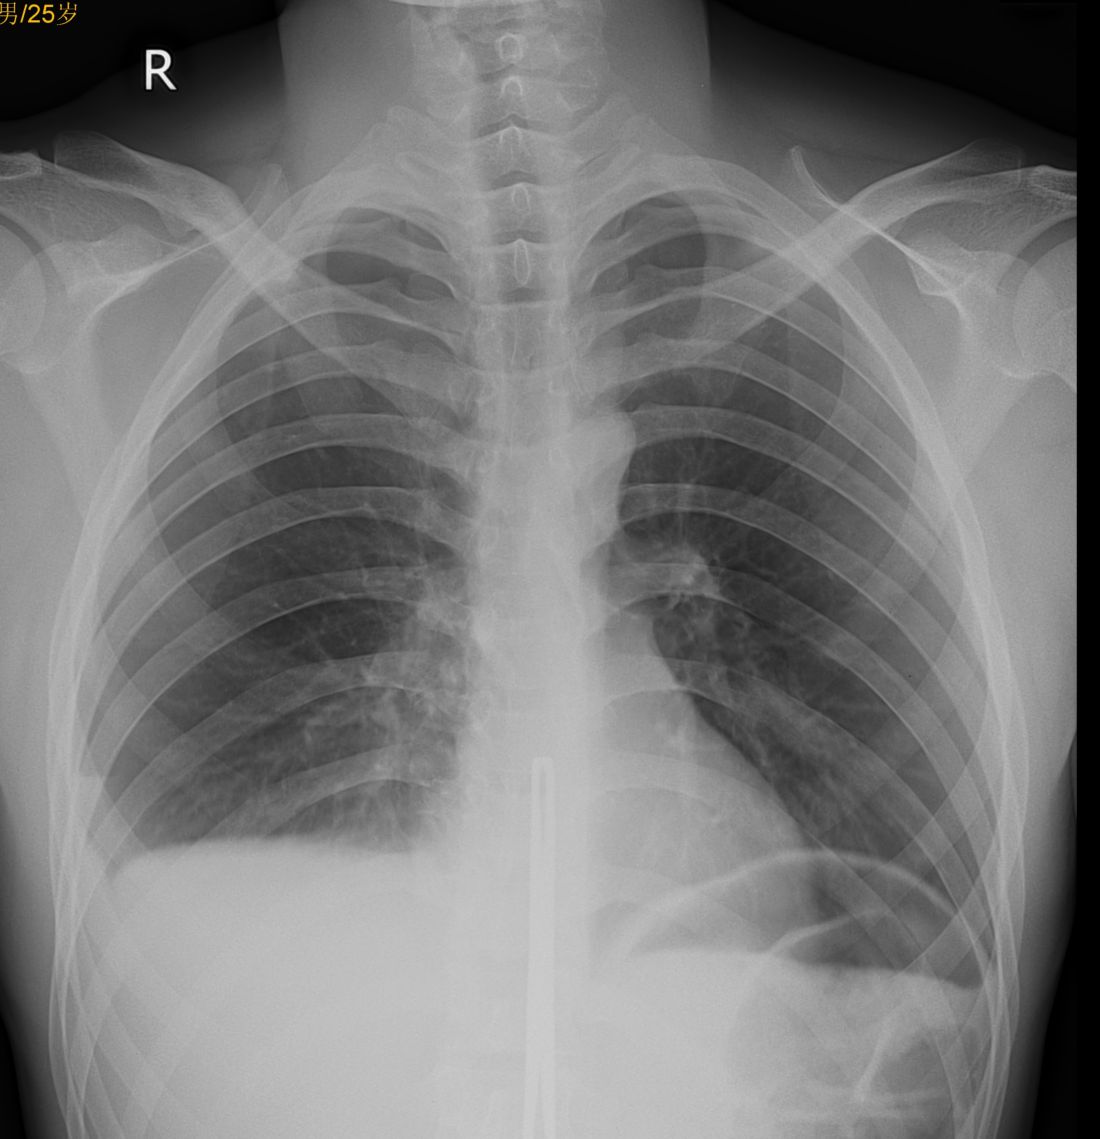

以下是引用dr.yang在2010-6-24 23:11:00的发言:[br]右侧血胸;[br]左侧膈下气腹;[br]胸腰段重叠处金属异物影

以下是引用sunbin在2010-6-25 12:49:00的发言:[br]右侧胸腔积液(血),建议ct检查。